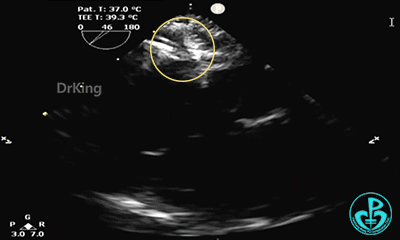

心脏位置及连接正常。各房室腔无明显增大,左室收缩活动可。主动脉三叶瓣,活动可。左右冠状动脉开口可见。肺动脉稍宽,瓣膜开放活动可。房室开放活动可;三尖轻度反流,反流速2.0m/s。房间隔缺损约5.4mm×5.2mm(继发型),近主动脉根部,缺损周围组织较薄软,距上腔静脉12.2mm,距右上肺静脉15.2mm,距二尖瓣环7.4mm,缺损下缘22.6mm,左向右分流为主,偶见右向左分流。沿室间隔未显示明显分流。

锁定后,主动脉短轴切面显示封堵器呈Y字型抱住主动脉根部。

主动脉短轴切面显示封堵器呈Y字型抱住主动脉根部,夹持稳定。